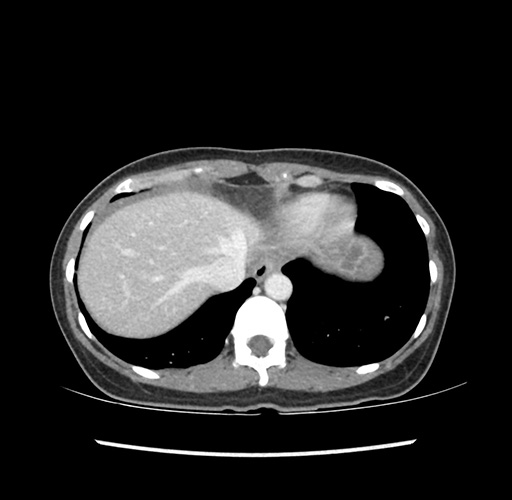

Imaging Analysis

Look through the patient's CT scan to identify any areas of concern for the necessary procedure.

Based on your CT findings, which issue(s) would give reason for "planned slowing down moment(s)" in this case?

Considering a standard left lateral sectionectomy procedure, what step(s) of the operation would you do differently in this case ?